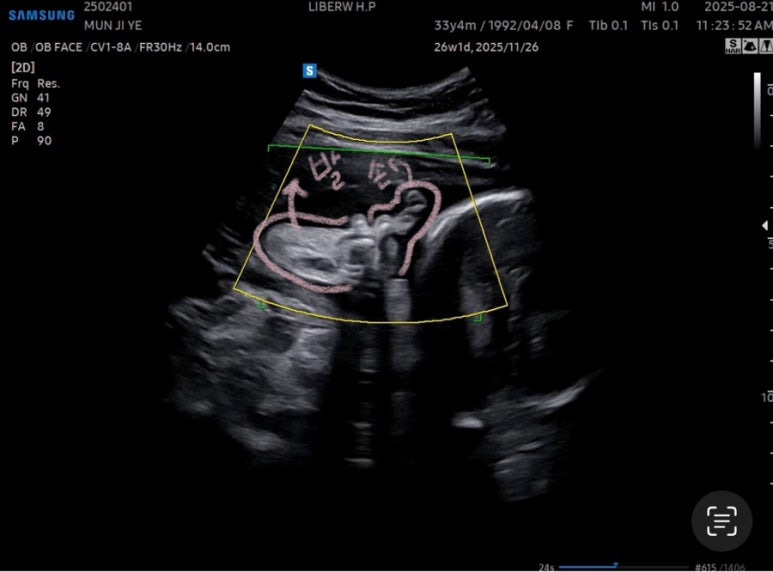

27주차 사탕이는

머리둘레 6.62cm

배 둘레 22.91cm

다리길이 4.61cm

몸무게 956g

심장박동수 150bpm

경부길이 3.44cm

양수량도 적당했다